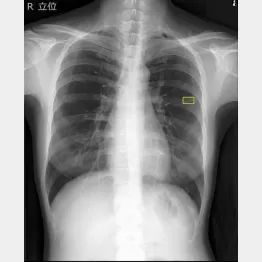

昨年8月に発売された「EIRL Chest Nodule(エイル・チェスト・ノジュール)」は、胸部X線画像から肺がんの可能性が疑われる「肺結節(陰影)」を検出するAI診断支援ソフト。医師単独で読影した場合と比べ、同ソフトを用いると感度が放射線専門医で9.95%、非専門医で13.1%向上することが認められているという。